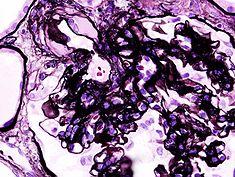

Diabetic glomerulosclerosis (1) HE.jpg

Microscopic image of diabetic glomerulosclerosis, the main cause of nephrotic syndrome in adults.

Diabetic glomerulonephritis in a person with nephrotic syndrome.

Secondary causes of nephrotic syndrome have the same histologic patterns as the primary causes, though they may exhibit some difference suggesting a secondary cause, such as inclusion bodies.[21] They are usually described by the underlying cause.